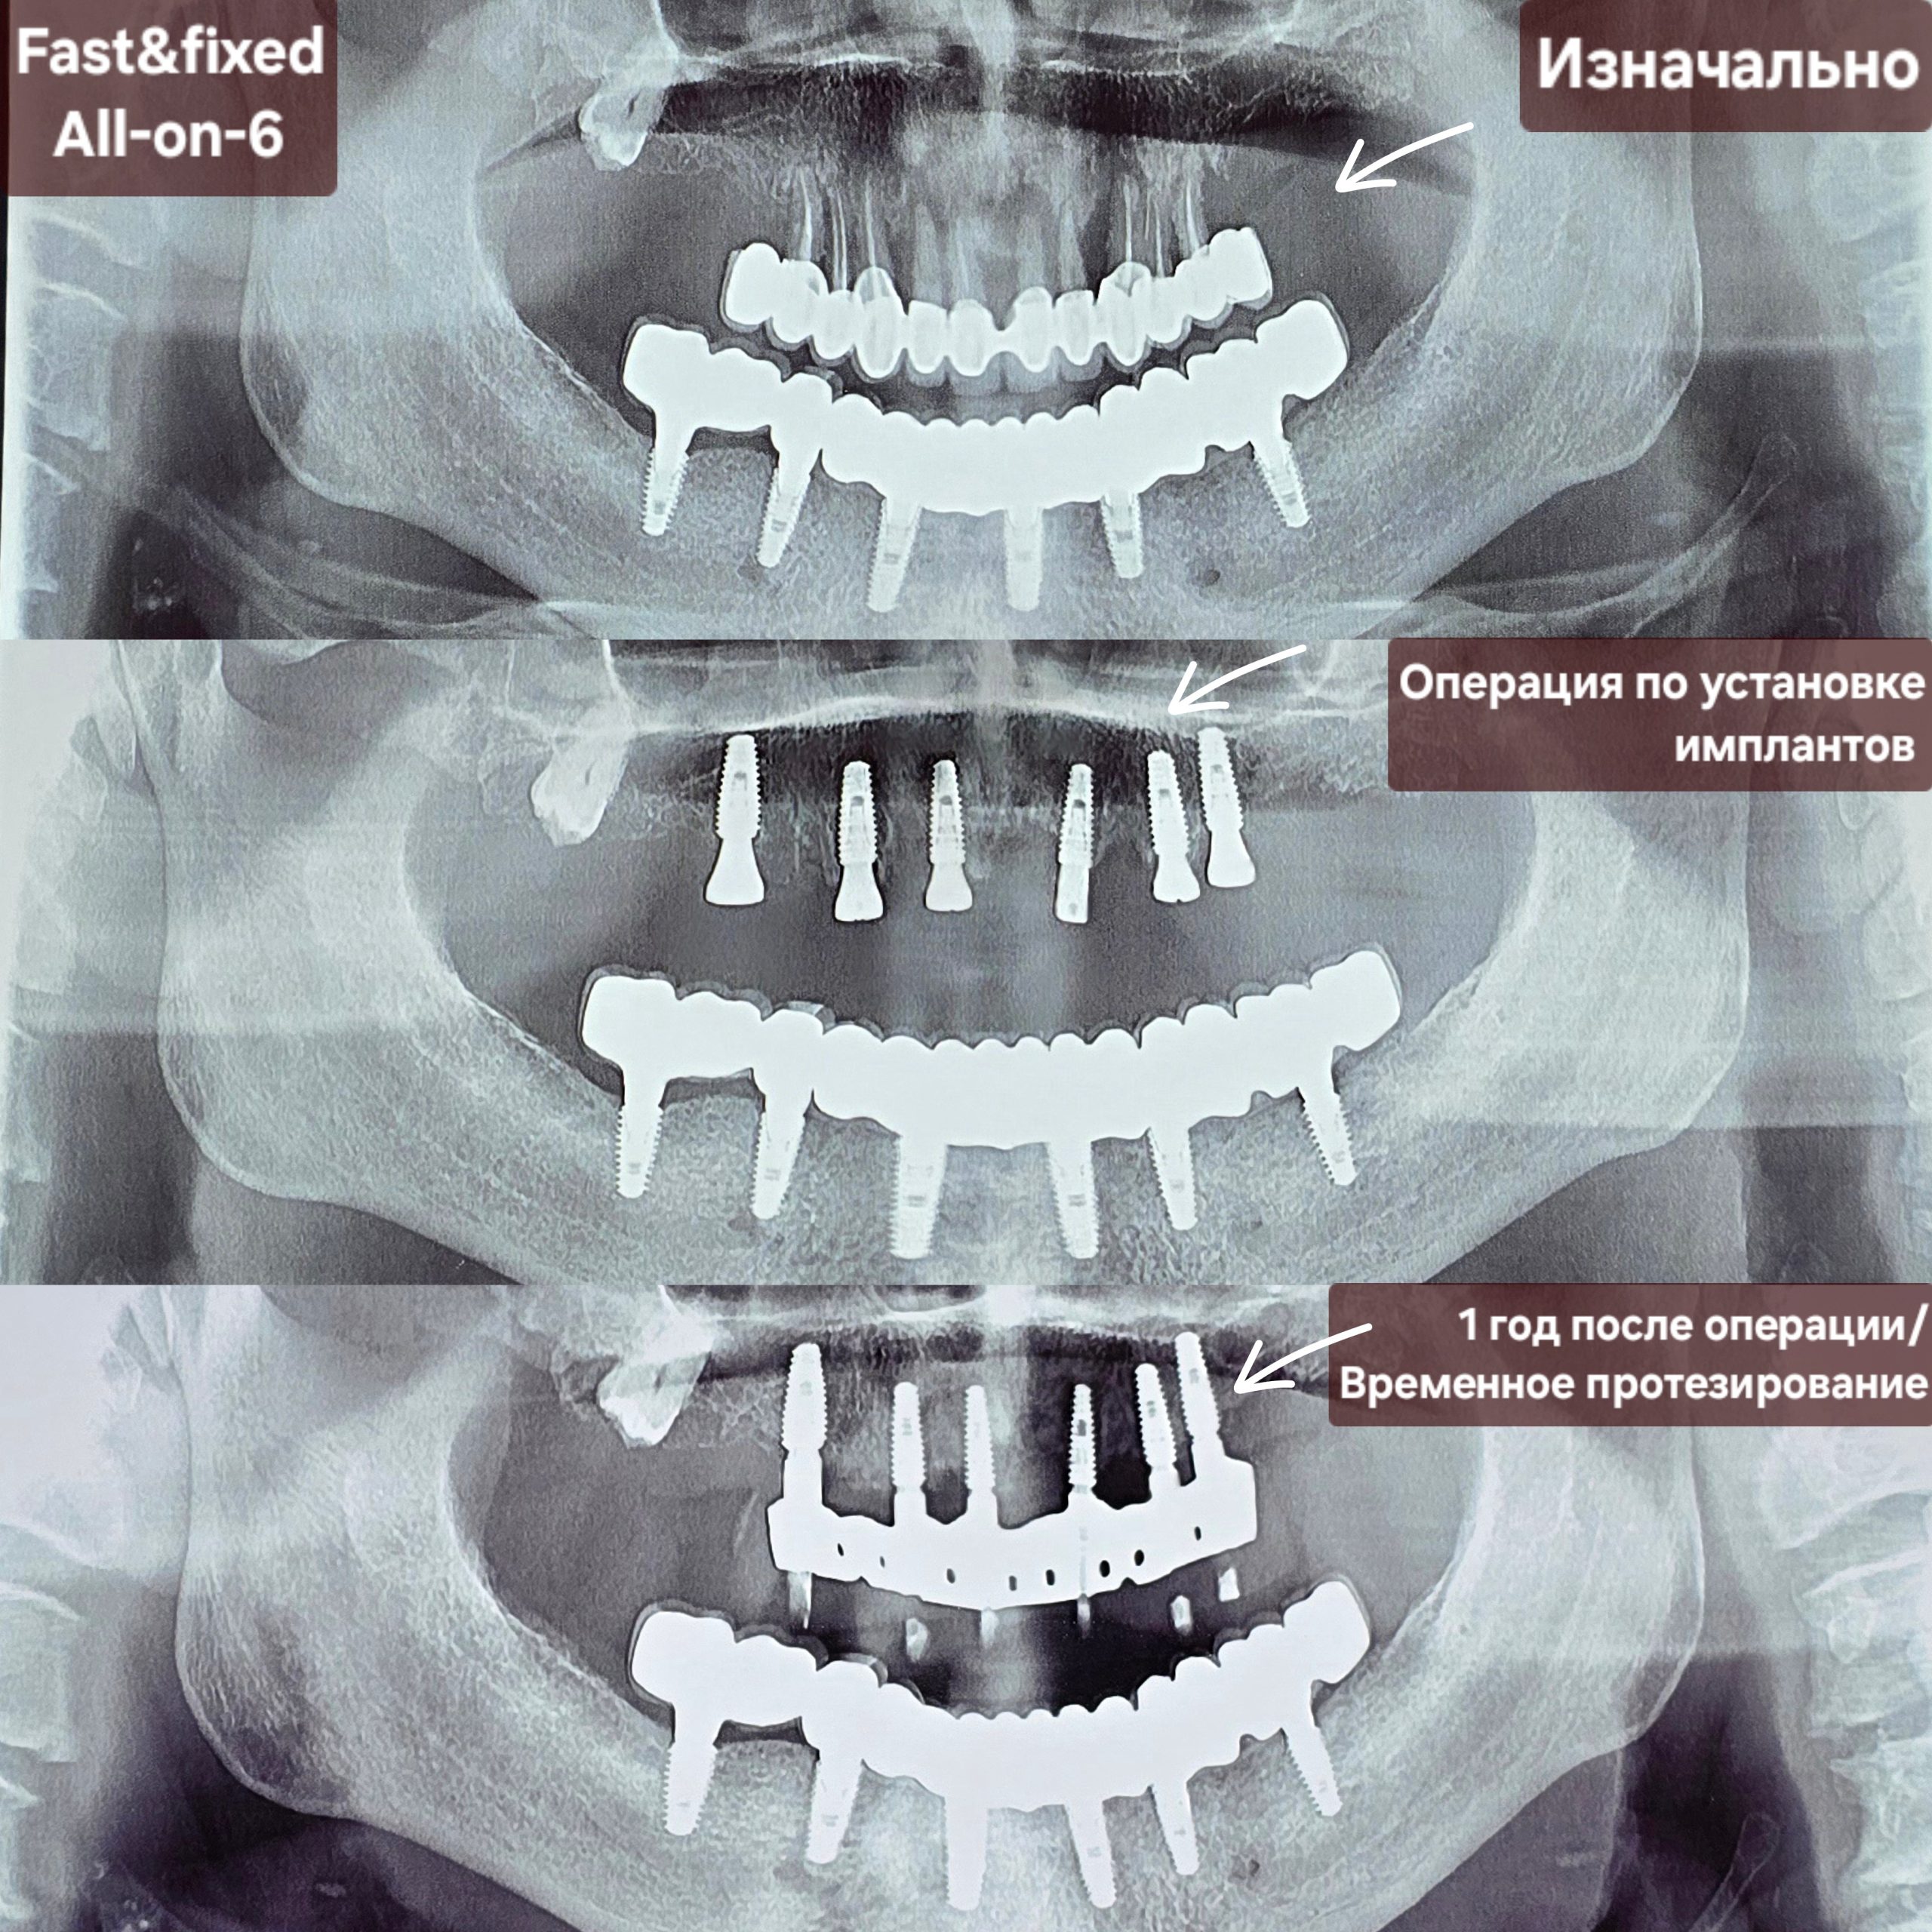

Хирургическое вмешательство

Следующий этап включает в себя установку зубных имплантатов в челюстную кость. При необходимости проводится удаление зубов, и кость подготавливается к установке имплантатов. В зависимости от плотности костной ткани пациента и общего состояния полости рта, на каждую челюсть может быть установлено от четырех до восьми зубных имплантатов. Имплантаты размещаются под углами, рассчитанными на обеспечение максимальной стабильности и поддержки протеза, а также равномерного распределения окклюзионных нагрузок.

Фиксация временного протеза

После операции по установки имплантата будет зафиксирована временный фиксированный протез. Это одно из главных преимуществ техники All-on-X, поскольку пациенты получают немедленное эстетическое решение, и уже через несколько дней смогут наслаждаться новой улыбкой. Помимо эстетических преимуществ, временный протез также способствует восстановлению жевательной функции.

Период заживления

Фаза заживления и интеграции имеет решающее значение для успеха лечения с помощью системы All-on-X. После установки имплантатов обычно требуется период заживления в несколько месяцев (минимум 6 месяцев) для их интеграции в окружающую костную ткань, этот процесс известен как остеоинтеграция.

Окончательная фиксация постоянного протеза.

После того как зубные имплантаты полностью срастутся с челюстной костью, стоматолог заменит временный протез постоянным. Это несъемный мостовидный протез из металло-керамики или циркониево-керамического материала, имитирующий внешний вид и функцию естественных зубов, чтобы пациент мог наслаждаться своей новой улыбкой.